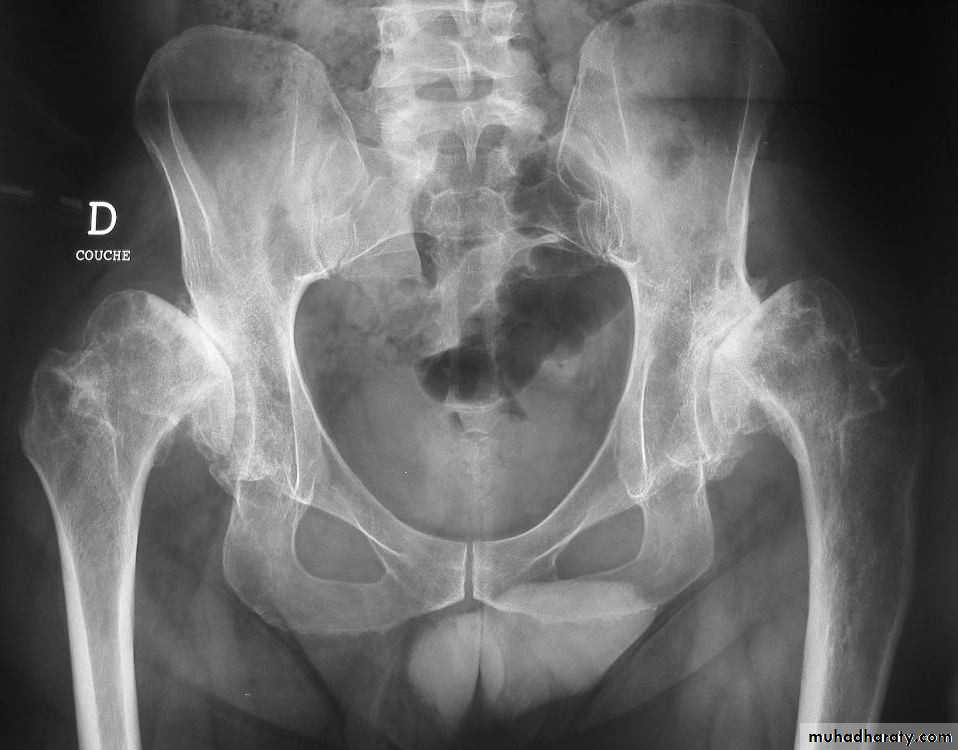

ANKYLOSING SPONDYLITIS (AS)

• Seronegative spondyloarthropathy of the axial skeleton and proximal large joints.• Clinical: males >> females. HLA-B27 in 95%. Insiduous onset of back pain and stiffness. Onset: 20 years.

• Radiographic features

• * SI joint is the initial site of involvement:

• bilateral, symmetrical

• Erosions: early ,Sclerosis: intermediate , ankylosis: late

• * Contiguous thoracolumbar involvement

• Vertebral body "squaring": early osteitis

• * Syndesmophytes

• * Bamboo spine: late fusion and Bamboo spine

• ligamentous ossification

• *ankylosed spine (fracture)

• * Enthesopathy is common(("whiskering of tuberosities )

• * Arthritis of proximal joints (hip > shoulder) in 50% ,erosions and osteophytes